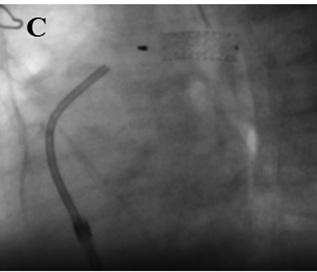

Three months after the hybrid procedure, percutaneous cerclage removal (Figure 2A and 2B) and ductal stent occlusion (Figure 2C) are carried out.

Fig.

2. Angiography. Dilation of both pulmonary branch cerclages

(A and B). Percutaneous ductal stent occlusion (C).